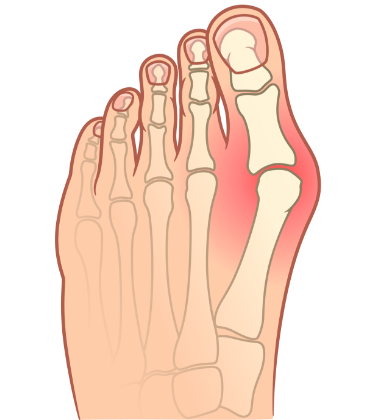

PRIJE

Stopalo deformirano čukljem - izbočene kosti, oteklina i žuljevi uzrokuju bol i otežavaju hodanje.